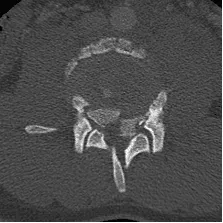

18 yo fell from 3 floors. Near complete loss of all neurological functions below the level of injury with near complete involvement of bowel and bladder

Patient was operated and the spinal canal cleaned up of all bony fragments. The spine was fixed from the side and the back to take care of instability.